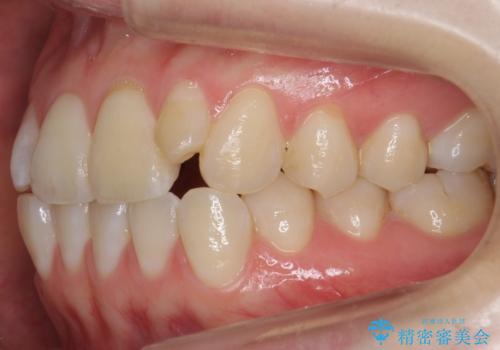

前歯が気になる 大人のマウスピース矯正 矮小歯を整える

- 前歯の並びを主訴に来院。

マウスピースで歯を抜かずに治療しています。

左上の前歯が飛び出しており、唇が笑った時に引っかかっていたのが解消しています。

左上の前歯は小さいため、(矮小歯)左右対称になるようにセラミックで形を修正する治療も併用しています。

歯を大きくかぶせるスペースを作るため、右上の奥歯を後ろに下げています。

左にずれていた上の正中も揃い、大変喜んでいただきました。